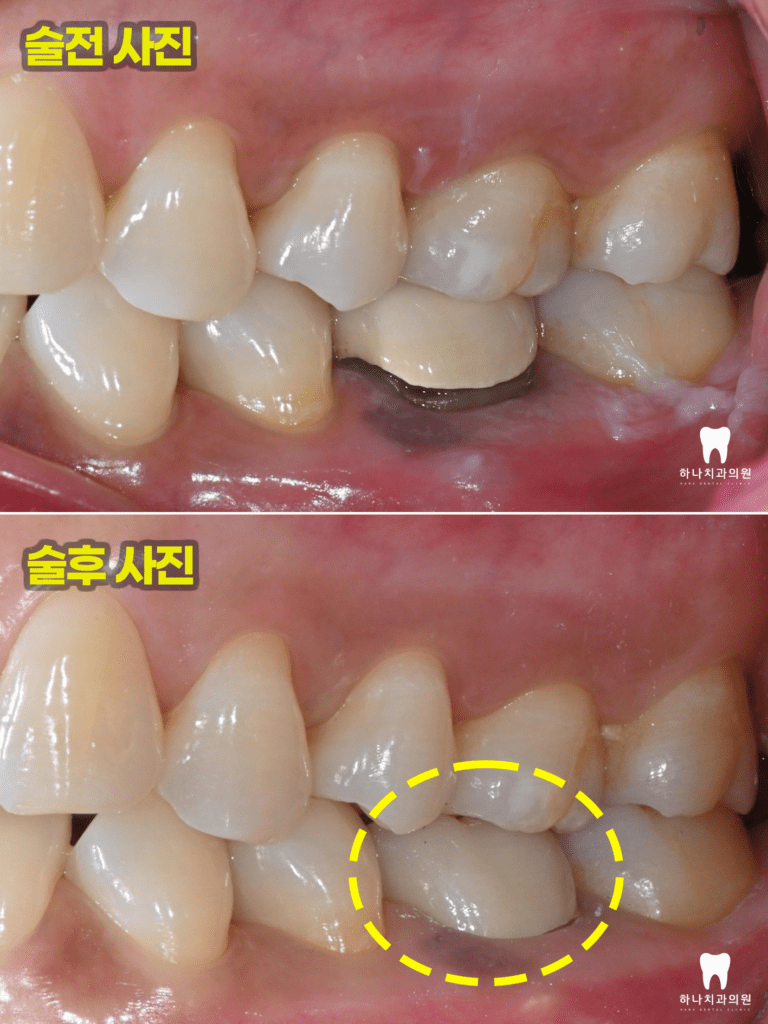

위 환자분께서는 40대 여성분으로

울산삼산동치과 하나치과

홈페이지 블로그를 통해 재신경치료

성공 케이스를 보시고 멀리 북구에서

내원해 주셨습니다.

타 치과에서는 발치를 권유받으셨다고

말씀해 주셨다고 하시며 재신경치료를

받아볼 수 있냐고 여쭤보셨는데요.

우선 치아의 동요도가 없고

염증의 형태가 치근단에 집중되어 있어서

재신경치료를 시도해 보자고 말씀드린 후

진행하기로 하였습니다.

우선 CT 촬영 후 사진에서 보았을 때

원심 근관의 충전을 보면 중앙을

충전물이 지나지 않는 것을

확인할 수 있었습니다.

모든 근관은 치근의 중앙을 지난다는

원칙에 위배되어 하나의 근관이

더 있다는 결론을 도출할 수 있었는데요.

먼저 기존의 크라운을 제거하고

재신경치료를 시작하였는데요.

이미 충전된 3개의 근관 충전물을

모두 제거하고 처음 치료 당시

찾지 못했던 숨은 근관도 1시간

넘는 시간을 들여 찾아내었습니다.

4회에 걸쳐진 치료를 완료하고

근관의 완전한 확보, 세척, 충전을

완료한 뒤 마무리 후 본뜨기 전의 모습입니다.